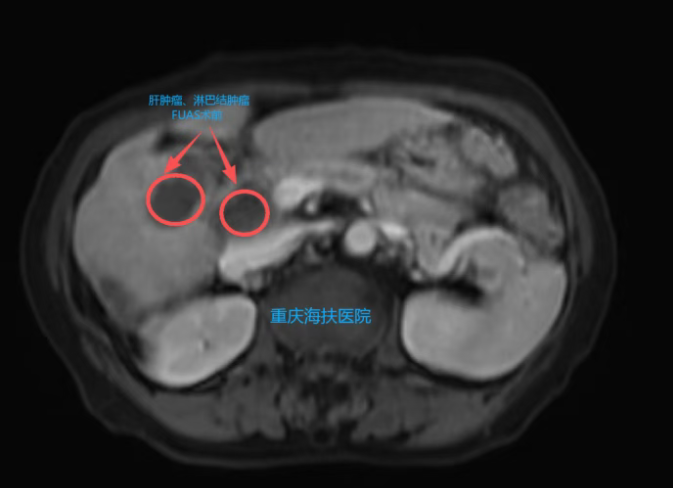

患者3个多月前体检发现肝脏占位,在澳门检查提示AFP升高,穿刺病理为分化不良癌,伴局灶性神经内分泌分化。随后在广东医院检查发现:肝脏S5段恶性肿瘤约4.0cm×3.1cm×5.0cm,同时伴门静脉癌栓及肝门区淋巴结转移。患者曾接受肝动脉化疗栓塞术并口服靶向药,症状有所缓解,但多处病灶仍未得到根治。

门静脉癌栓是肝癌治疗的公认难点,常规手段难以彻底处理。在多方了解后,患者选择接受聚焦超声消融手术(FUAS)。

术后第1天,患者已进流食,无明显疼痛,仅轻微腹胀,复查指标整体平稳。复查MRI显示:消融区域肿瘤坏死明显,“黑洞”征清晰,提示病灶已被灭活。